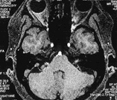

2.面部检查:在做常规检查前,患者可行初步自我检查,如两侧眼睛是否对称、皱眉时两侧幅度是否一致、抬眉时是否出现额部皱纹等;常规检查以肌电图及脑电图检查为常见,用电刺激患侧眶上神经时,同侧眼轮匝肌及其他面神经支配的肌肉出现同步收缩,这是本病的主要特点。正常者或其他面部疾病者进行此检查时,仅引起患侧眼轮匝肌的收缩;为排除乳突及颅骨病变,应进行乳突及颅骨X线摄片、头颅CT及MRI,以进行终确诊。

面肌痉挛疾病的成功治疗,首先是有高场强磁共振技术支持,使压迫神经的微血管在磁共振上一览无余。